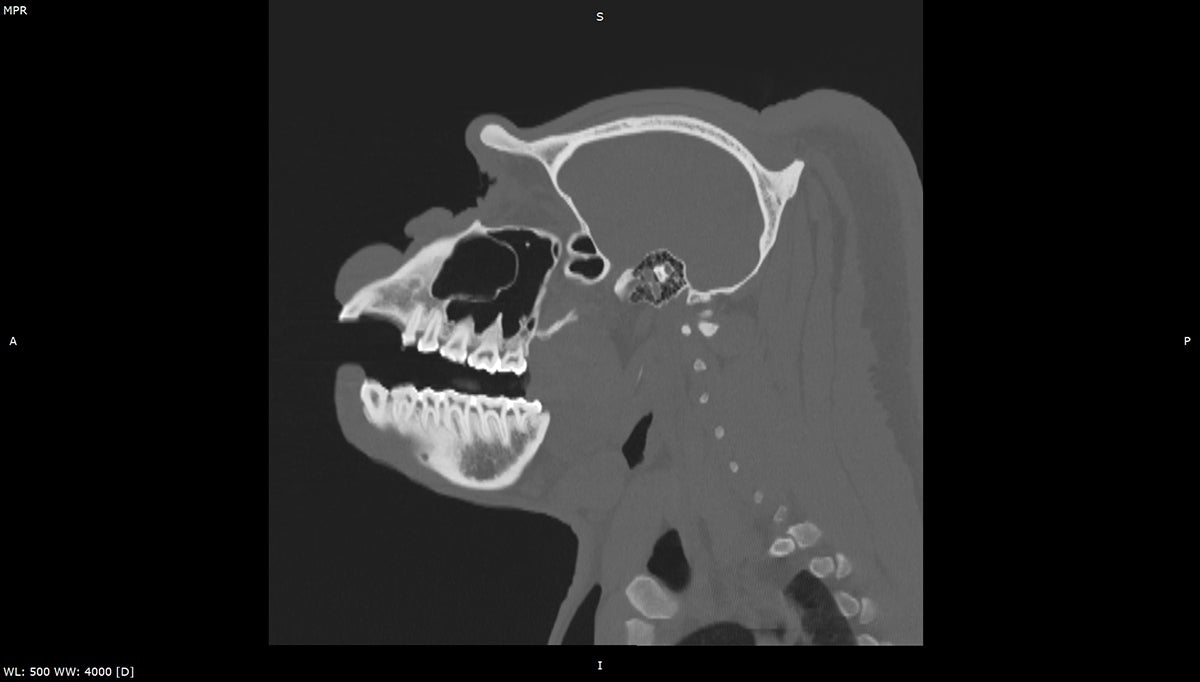

Much like your visits to the dentist, animals undergo everything from detailed tooth charting to advanced imaging such as X-rays or CT scans, helping identify problems before they could potentially become more serious conditions. Treatments can include cleanings, root canals, or extractions, providing each animal with care and support for their long-term health.

Take lions, for example. Lions rely on their powerful teeth as their multi-purpose tools. Their teeth are essential for gripping prey, devouring meals, and even baring them in defense and fighting. When Bo, a lion who lives at the Safari Park, recently came in for his routine exam, our team recognized that his “tools” needed special attention. The team performed a root canal on Bo’s right mandibular (lower jaw).

Another lion, named Ernest, was also recently treated as he needed root canals on two teeth—care neither big cat would have gotten in native habitat. Both lions were quickly on their way to recovery thanks to our team’s early action and expertise.